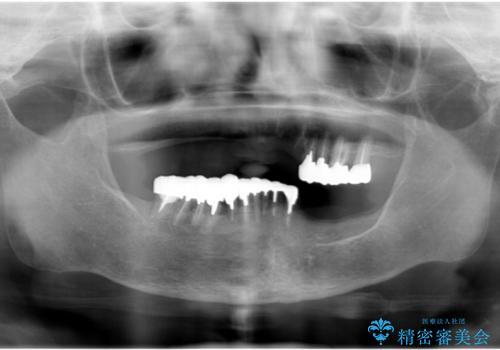

- 他院にて入れ歯を入れたが全体的に左に傾いており、咬みにくく、見た目も気になるといらっしゃった方の症例です。

診査の結果、虫歯が進行し保存できない歯が多かったため抜歯し、磁性アタッチメントを用いたインプラントオーバーデンチャーによる咬合及び見た目の改善を行いました。

当院では主にストローマンという種類のインプラントを治療に用いています。

ストローマンは世界的にもNo1のシェアを誇り、骨との適合にも優れたインプラントです。